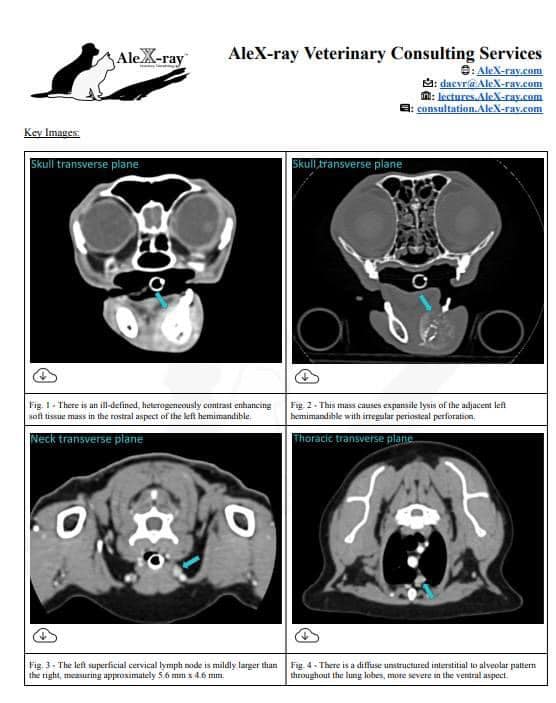

狗狗電腦斷層掃描 不明原因口腔出血 嚴重牙周病 口腔惡性腫瘤 鱗狀上皮細胞癌(Squamous cell carcinoma,SCC)

主訴嘴巴突然流血 口腔潰爛 左下顎腫脹 同時有嚴重牙周病 經由口腔採樣 電腦斷層掃描 確認為鱗狀上皮細胞癌(Squamous cell carcinoma,SCC)同時已經侵犯下顎骨。確診後經由外科醫師、腫瘤科醫師、電腦斷層影像科醫師共同擬定治療計畫後

,大範圍切除左下顎,經過一年追蹤,目前狗狗一切安好喔。

*電腦斷層影像

貓咪 下顎骨骨折

頭骨結構較為複雜 頭骨骨折相對於四肢長骨骨折 不容易靠xray 完整評估術前需要靠電腦斷層影像檢查評估骨折狀況才能良好評估手術方式 提高成功率